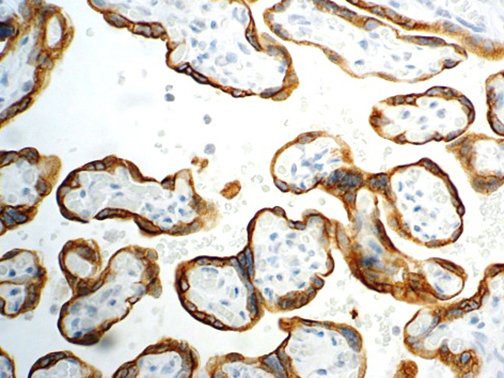

This activation induces inflammatory monocytes to highly express IL-6, starting a localized and then systemic cascade effect that results in hyperproduction of IL-6, which accelerates the inflammatory process. Because IL-6 also increases vascular permeability, excessive levels cause blood vessels to become very leaky. This, along with clotting factors released from vascular endothelial cells, stimulates the coagulation cascade, resulting in microthrombosis (tiny clots), which leads to ischemia and tissue death of the kidney, intestines, heart, liver, brain and extremities.